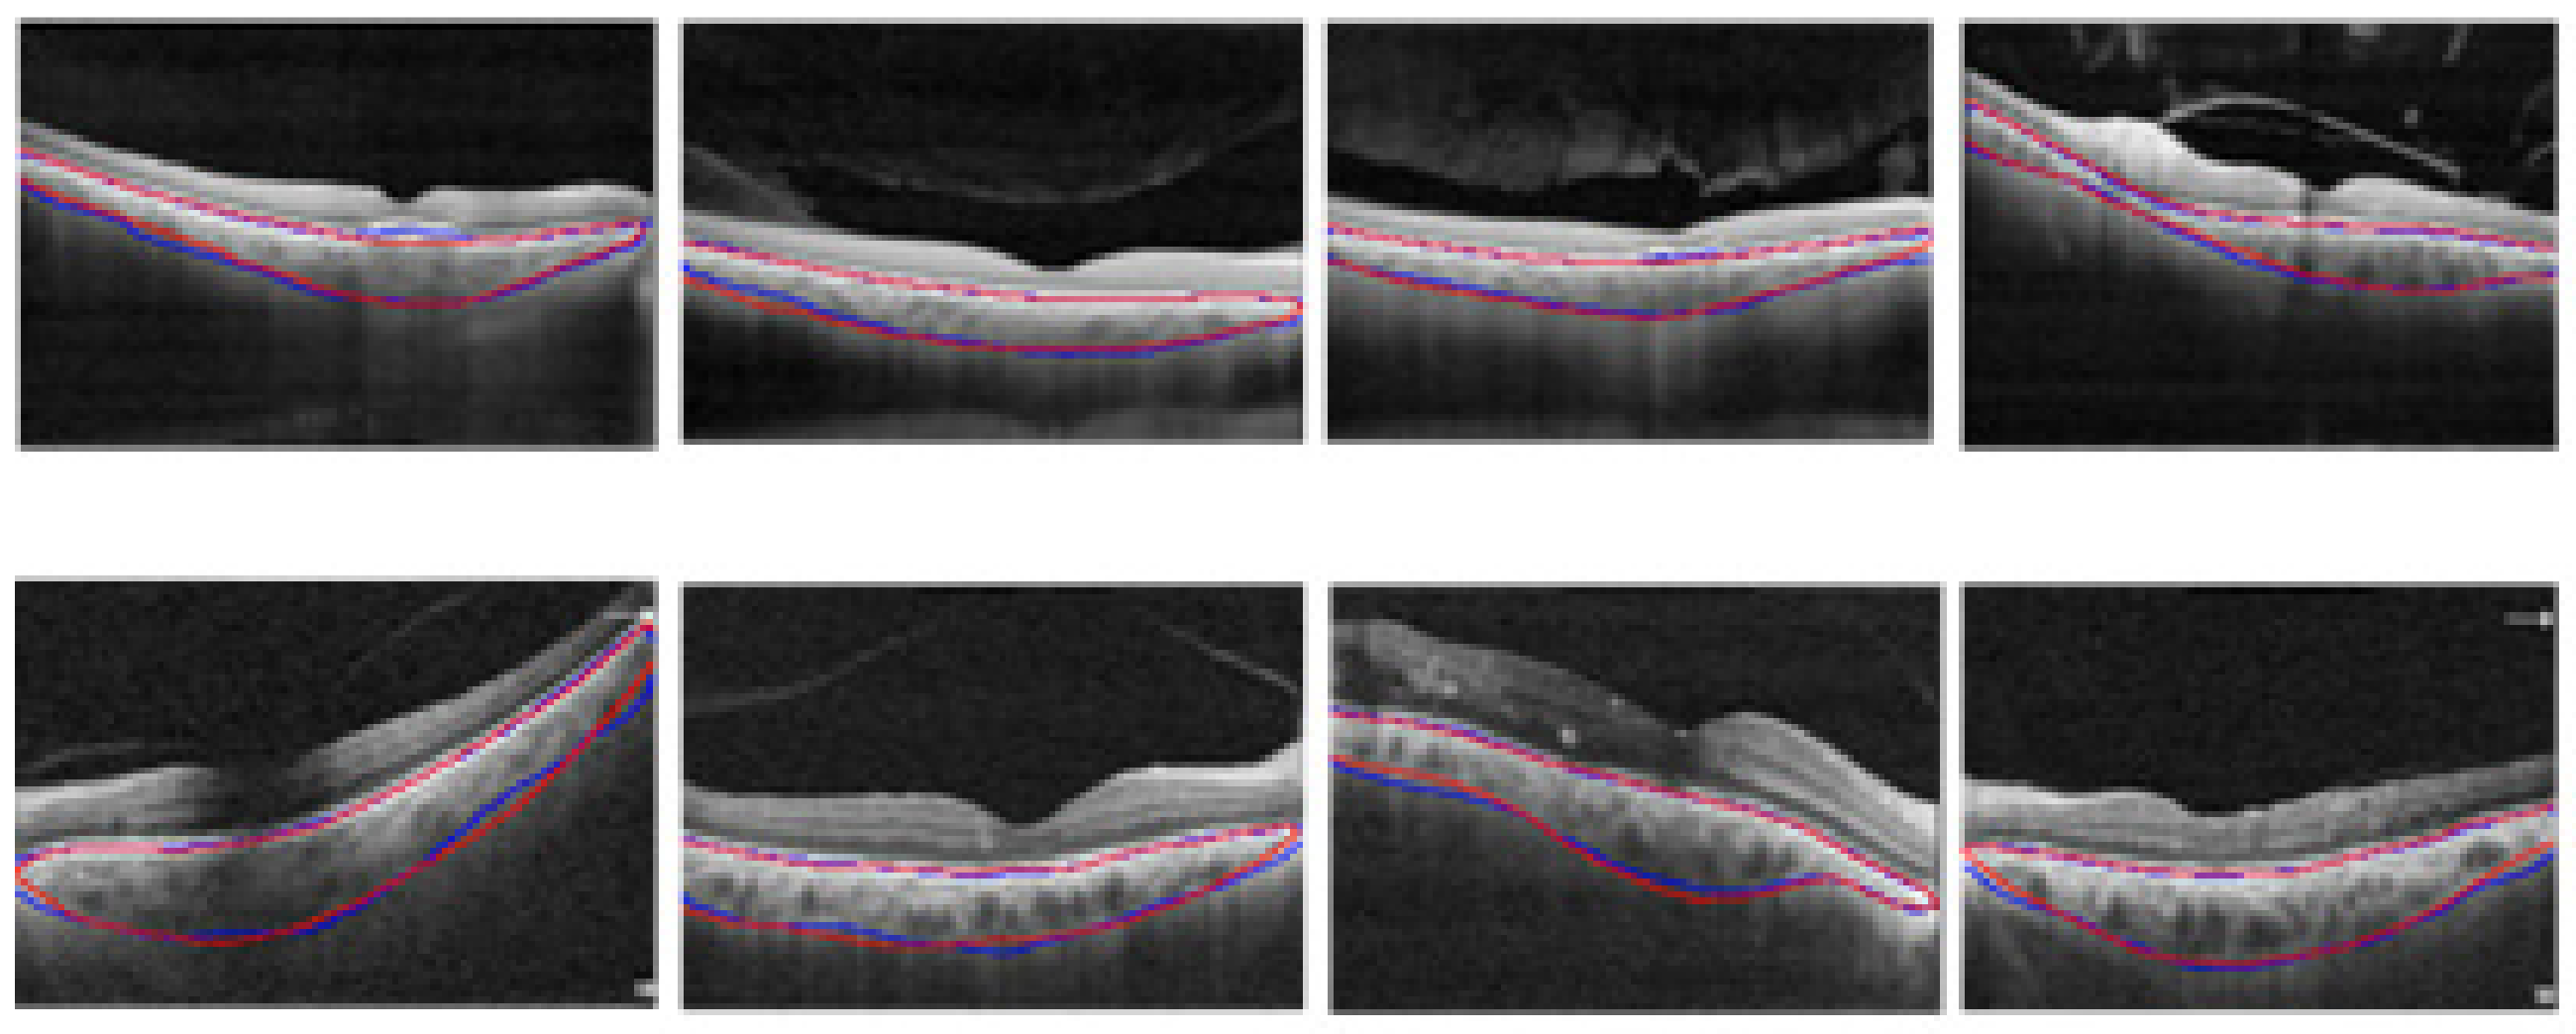

- The proposed modified U-Net segmented the choroid and BM boundaries in challenging cases such as low-contrast images with thickened choroidal areas.

3.1. Choroidal Boundary Segmentation in Pachychoroid Spectrum Dataset

3.2. Choroidal Boundary Segmentation in the Diabetic Retinopathy Dataset